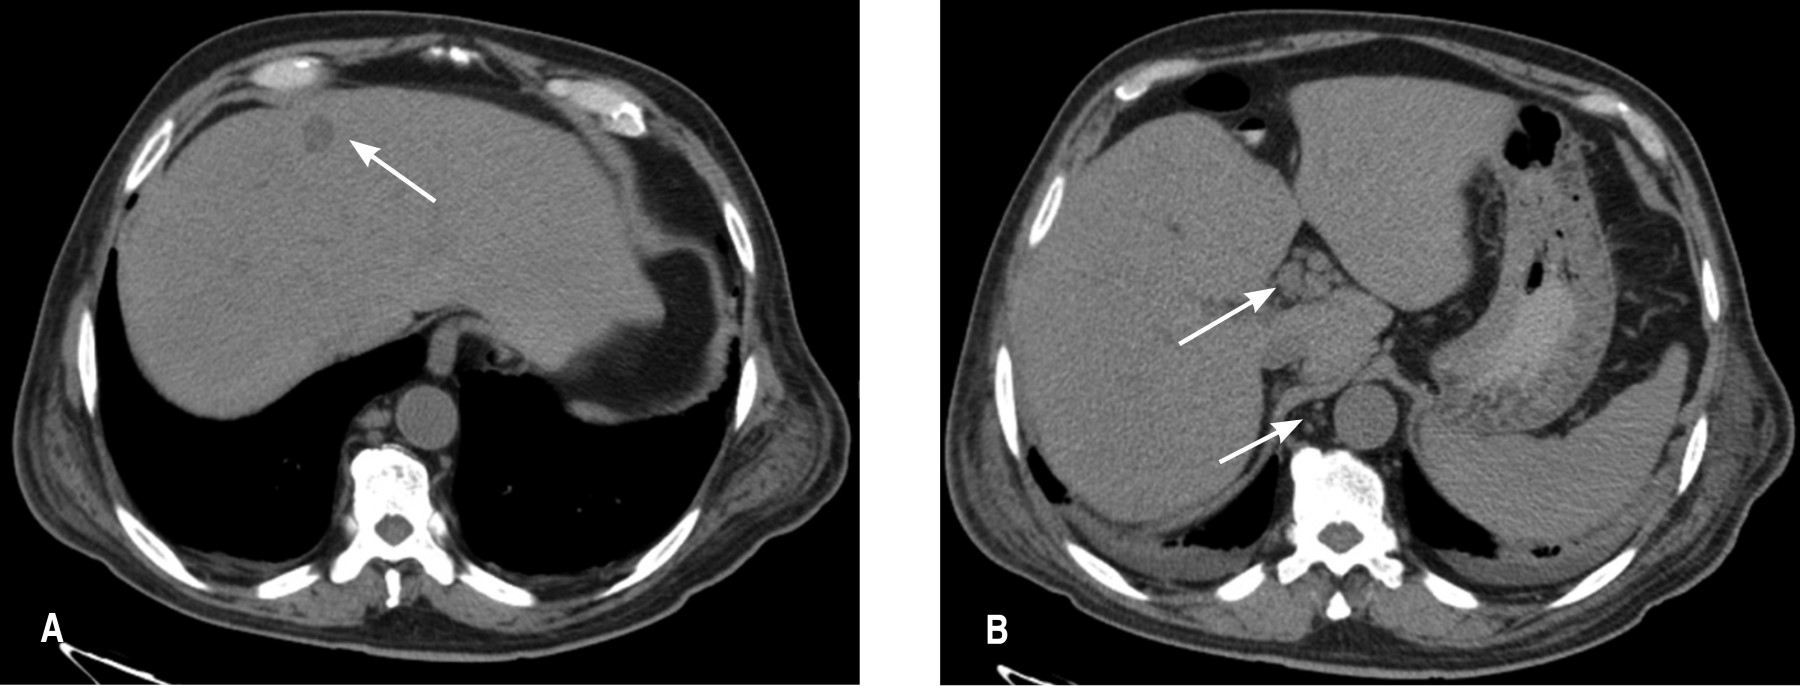

He was clinically stable, with a distended abdomen, painful in the right hypochondrium and right iliac fossa. Laboratory studies reported leukocytes 2.8 × 103/µl, total neutrophils 87.8%, hemoglobin 6.7 g/dl, hematocrit 20.2%, platelets 67 × 103/µl, total bilirubin 3.04 mg/dl, direct bilirubin 2.16 mg/dl, indirect bilirubin 0.88 mg/dl, and negative viral panel. Ultrasound of the liver and bile ducts reported chronic lithiasic cholecystitis with hepatomegaly. An abdominal CT scan reported lymph node growth at the hepatic hilum. Also, peripancreatic, phrenic, paracolic, and paraintestinal, as well as precaval, retrocaval, interaortocaval, and para-aortic nodes were found. The liver had images of possible metastatic implants in segments IV and VI. The gallbladder had a 6.3 mm wall, with hypodense content, changes due to cholecystitis and scarce perihepatic fluid (Figure 2).

Figure 2